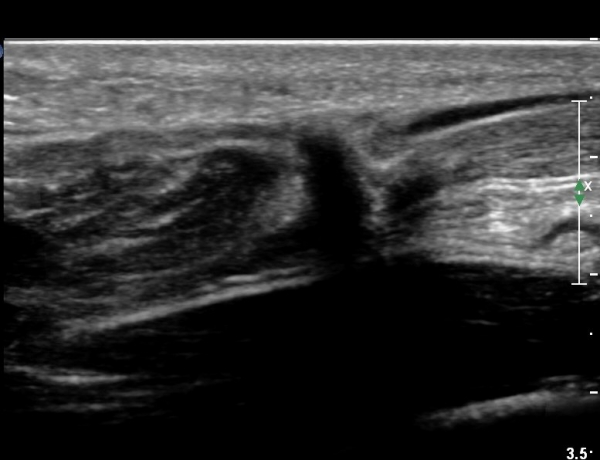

¾ÆÅ³·¹½º°Ç Ⱦ´Ü¸é°Ë»ç¿¡¼ ¾ÆÅ³·¹½º°Ç Àú¿¡ÄÚ ºÎÁ¾, ¿¬°á¼º ¼Ò½Ç, °ÇÁÖÀ§ ¼ö¾×Àú·ù ¼Ò°ßÀ» º¸ÀÓ(»çÁø 6, 7, 8).